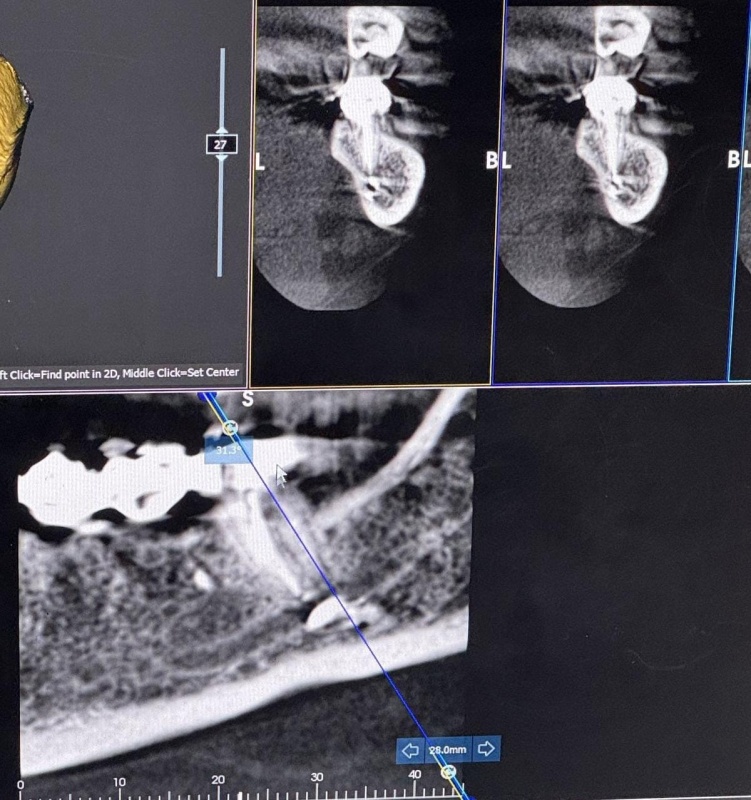

R.Zaxarova bununla bağlı Səhiyyə Nazirliyinə müraciət etdiyini, lakin özəl müəssisə olduğu üçün məsələyə laqeyd yanaşıldığını deyib: "Bütün bu müddət ərzində məsuliyyət daşıyan tərəf mənə heç bir köməklik göstərmədi. Həkim məni başqa bir həkimə yönləndirəcəyini dedi, lakin onu da etmədi. Əlimdə rentgen görüntüləri və əməliyyat sənədləri var".